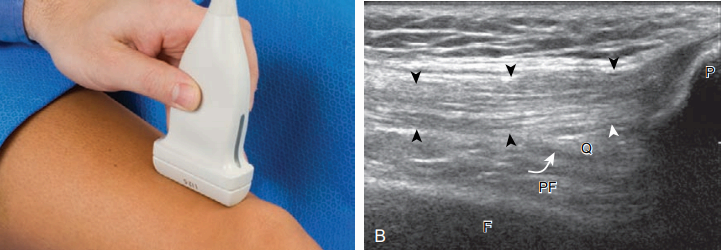

앞쪽에서 검사해야 할 기본 구조물에는 네 갈래근힘줄, 무릎힘줄, 무릎지지띠, 무릎위오목, 그리고 무릎앞쪽의 윤활주머니 등이 있다. 검사는 무릎뼈 위쪽에서 시상면으로 시작하며, 이때 정상적으로 에코가 높고 가는 섬유다발의 양상을 보이는데 네 갈래근힘줄을 볼 수 있다.

무릎 뒤에 받침을 받쳐 무릎을 약간 굽히는 것이 도움이 되는데, 이런 자세가 폄기전(extensor mechanism)에 관계있는

구조물들을 곧고 팽팽하게 함으로써 비등방성 효과(anisotropic effect)를 감소시키기 때문이다. 네 갈래근힘줄은 흔히 세 겹으로 보이는데, 넙다리곧은근(rectus femoris)이 가장 얕은 층, 안쪽 및 가쪽 넓은 근(vastus medialis and lateralis)이 합쳐져서 중간층, 중간 넓은 근(vastus intermedius)이 가장 깊은 층을 형성한다. 네 갈래근힘줄의 더 깊이에 무릎위오목이 있는데 '에코 없음'(anechoic) 혹은 '낮은 에코'(hypoechoic)로 보이는 관절액 유무를 검사한다. 관절액이 있으면 앞쪽의 네 갈래근 지방덩이와 뒤쪽의 넙다리뼈 앞 지방덩이를 더 잘 구분할 수 있다. 무릎을 약간 굽히면 다른 부위의 관절액이 무릎위오목으로 이동된다. 그다음 탐촉자를 시상면으로 무릎뼈 아래로 옮겨서 균일하게 높은 에코와 가는 섬유다발(fibrillar) 양상의 무릎힘줄을 검사한다.